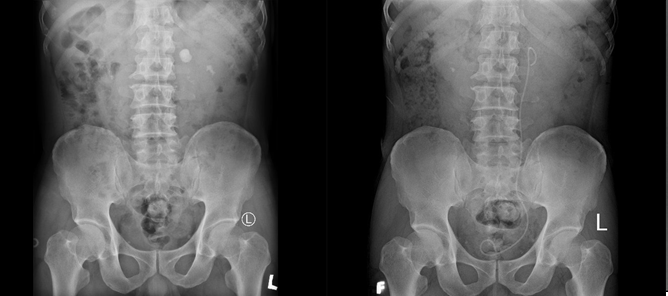

(Baothanhhoa.vn) – Bệnh viện Đa khoa tỉnh Thanh Hóa vừa tiếp nhận và phẫu thuật cấp